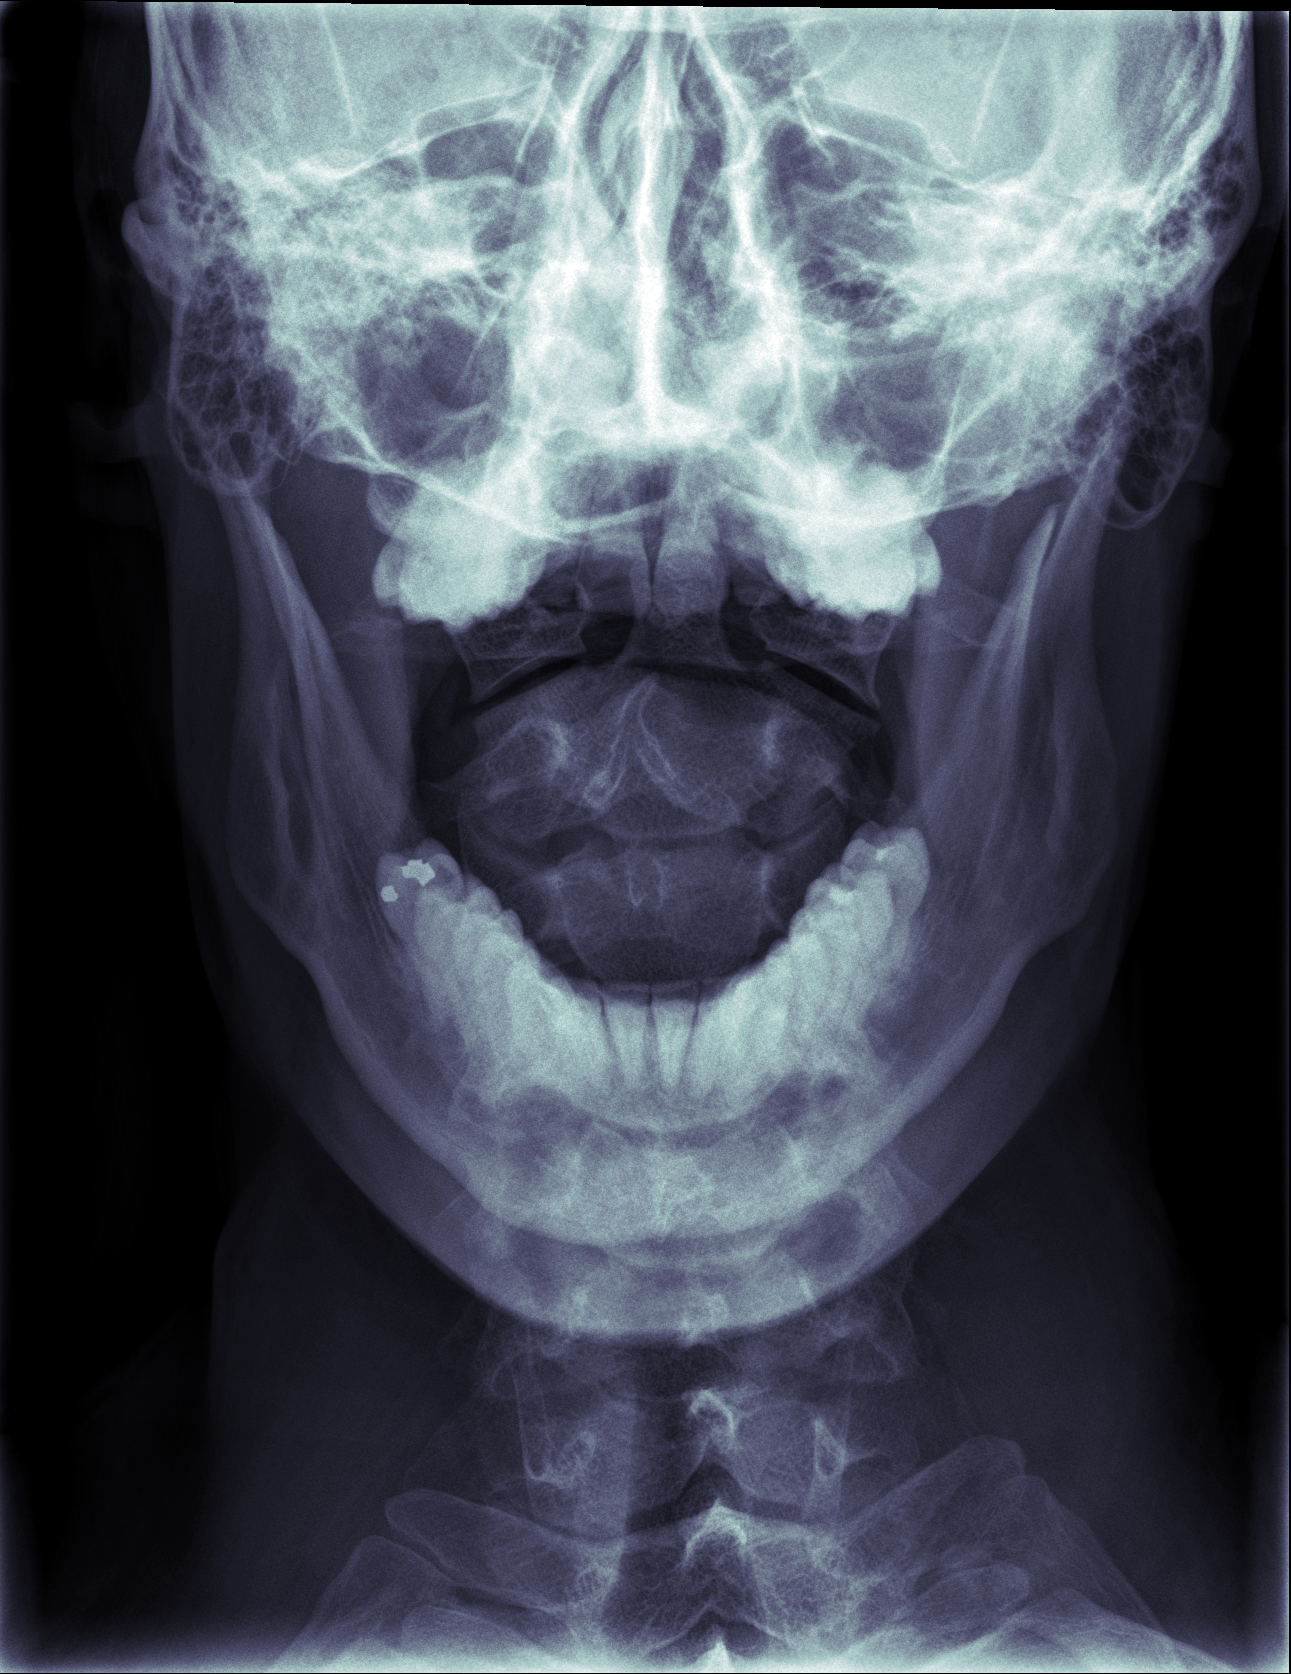

For this one the tech had me open my mouth so he could see the front of some of my upper vertebrae through the aperture between my teeth.

It’s also extra freaky, like something out of Alien.